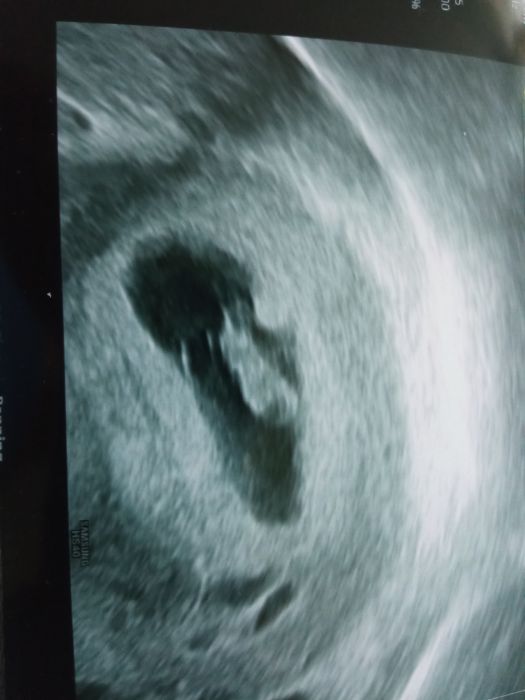

Holky, my jsme jeli ještě v pondělí na gyndu a miminko vypadalo v pořádku, o 5dni mladší, srdíčko bilo...jen prostě ty testy vycházejí slabé, takže uvidím, jak to dopadne...není mi ani pořádně špatně, jako mi bylo u všech 3deti...a teď ještě musím přemýšlet, jestli to zvládnu se 4detmi...chlap se včera rozhodl, že má rymicku, takže už 2.den leží a nic nedělá, jsem na něj naštvaná, protože když jsem nemocná já,tak můžu normálně makat a on nás všechny odepíše a stará se jen o sebe...když jsem mu včera řekla,ať dětem nejí pomazánku, že nebyl na nákupu a já pro ně nic jiného nemám,tak rozbil vzteky talíř...těžko můžu jít na nákup, když dcera včerejšek prozvracela a nejmladší má kašel a nudli...prostě je na něj spolehnutí, tak mám důvod k zamyšlení...